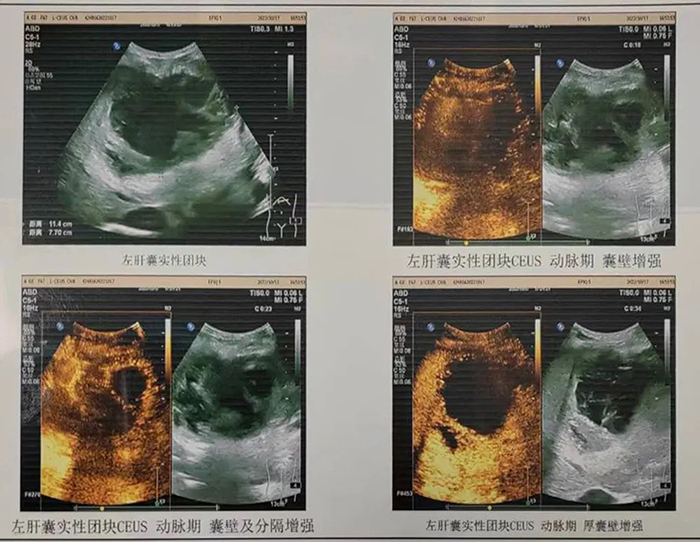

通過耐心做患者家屬工作,認(rèn)真細(xì)致地交待手術(shù)情況以及各項(xiàng)注意事項(xiàng),患者家屬簽署了手術(shù)知情同意書。同時(shí),術(shù)前為患者再次進(jìn)行了超聲造影檢查,確認(rèn)為典型肝膿腫表現(xiàn)。經(jīng)過充分評(píng)估適應(yīng)癥和禁忌癥,超聲科副主任趙仲舉醫(yī)生,黃軍醫(yī)生、黃建成醫(yī)生共同為患者實(shí)施超聲引導(dǎo)下肝膿腫置管引流。